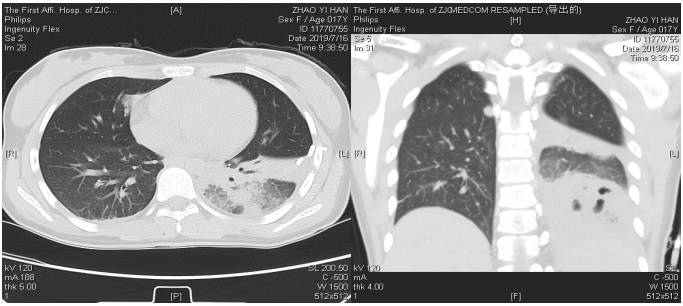

胸部CT:两肺多发斑片状及结节状高密度影,考虑炎性病灶,真菌类感染可能。

CT:两肺多发感染性病灶,部分病灶脓肿形成,左肺下叶部分膨胀不全版少量积液。